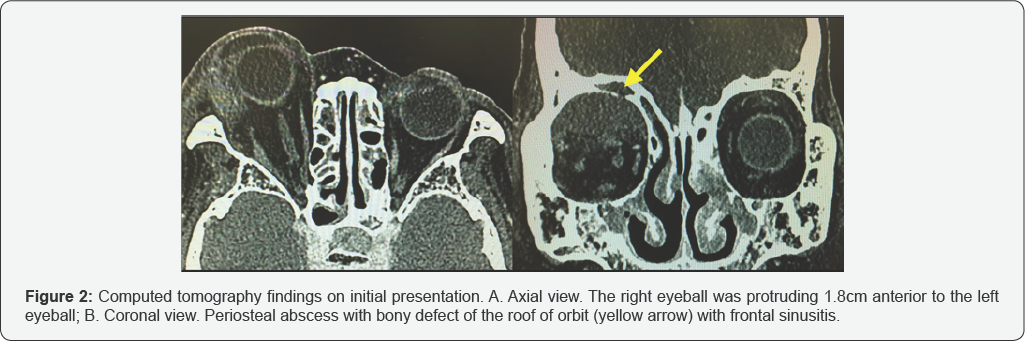

A 78-year-old woman presented with headache, a six-day history of swollen right eye, and a four-day history of gradually worsening visual disturbance, along with spontaneous vomiting. A physical examination showed severe swelling of her right eye with inflammation and severe edema of the conjunctiva, lagophthalmos, cataract ulceration, and exophthalmic ophthalmoplegia (Figure 1A & 1B). A visual accuracy test could not be performed. Computed tomography revealed a superior subperiosteal orbital abscess with the right eye protruding1.8 cm anterior to the left eye (Figure 2A & 2B).